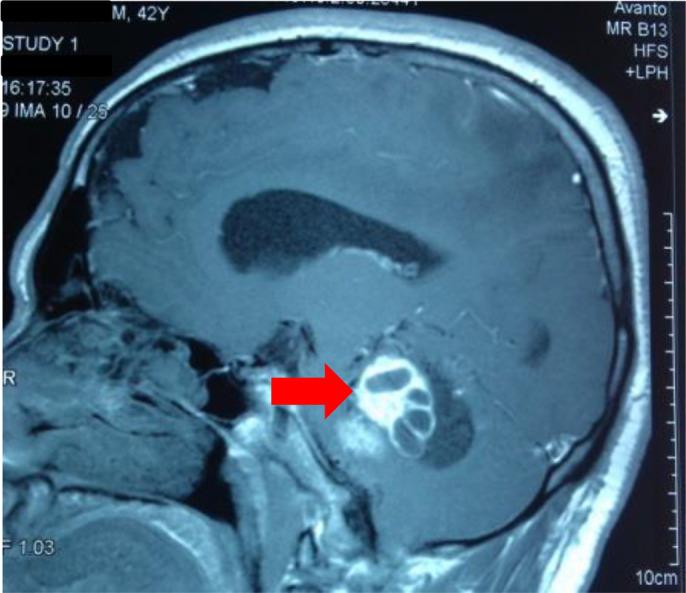

Tumors secreting catecholamines, such as pheochromocytomas and paragangliomas, are rare and life-threatening, due to their complications. They can be sporadic or occur in genetic syndromes, such as von Hippel-Lindau in which pheochromocytomas are observed in 10 to 20%. We report a case of a 42 years old male, who was sent in 2016 to our department for neurological symptoms related to cerebellar and central vestibular syndromes. His medical history revealed that at 8 years old he was operated for a symptomatic bilateral pheochromocytoma discovered by adrenergic symptoms and high blood pressure. Cerebral MRI showed intra- and extra-axial, supra- and infratentorial lesions causing supratentorial hydrocephalus associated with leptomeningeal dissemination deemed to be hemangioblastomas. One year later the patient started complaining of chronic diarrhea. The abdominal CT revealed three pancreatic tumors with radiological signs of pancreatic neuroendocrine tumors (PNETs) and a 12 mm mesenteric nodule presenting as a homogenously and typical for NET. The largest PNET had intensive fixation on octreotide scintigraphy. The association of pheochromocytomas, hemangioblastoma and pancreatic neuroendocrine tumors highlighted the diagnosis of VHL syndrome. The family history proved positive in a sibling with bilateral pheochromocytoma in infancy, retinal hemangioblastomas and cerebral hemangioblastoma. Genetic testing would have been useful, but in our case, it was lacking due to poor socio-economic conditions of the patient and absence of genetic testing in public hospitals.

分泌儿茶酚胺的肿瘤,如嗜铬细胞瘤和副神经节瘤,较为罕见且因并发症而危及生命。它们可以是散发性的,也可发生于遗传综合征中,如冯·希佩尔-林道综合征,其中10%至20%的患者会出现嗜铬细胞瘤。我们报告一例42岁男性病例,该患者于2016年因与小脑和中枢前庭综合征相关的神经症状被送至我科。他的病史显示,8岁时因由肾上腺素能症状和高血压发现的有症状双侧嗜铬细胞瘤接受了手术。脑部磁共振成像(MRI)显示轴内和轴外、幕上和幕下病变,导致幕上脑积水并伴有被认为是血管母细胞瘤的软脑膜播散。一年后,患者开始抱怨慢性腹泻。腹部CT显示三个具有胰腺神经内分泌肿瘤(PNET)放射学征象的胰腺肿瘤以及一个表现为均匀且典型神经内分泌肿瘤的12毫米肠系膜结节。最大的PNET在奥曲肽闪烁扫描中有强烈摄取。嗜铬细胞瘤、血管母细胞瘤和胰腺神经内分泌肿瘤的关联突出了冯·希佩尔-林道综合征的诊断。家族史显示一名同胞呈阳性,其在婴儿期患有双侧嗜铬细胞瘤、视网膜血管母细胞瘤和脑血管瘤。基因检测本会有用,但在我们这个病例中,由于患者社会经济条件差且公立医院缺乏基因检测而未能进行。